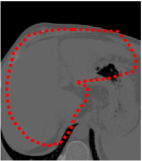

An example of CT/CBCT and MR/CBCT registration results are shown in figures 3 and 4, respectively. For both cases, the CBCT image (first column) was acquired intra-operatively after needle insertions and was employed as a reference for image registration. The pre-operative image is displayed before registration (second column), after PM-EA (third column) and after PM-EA+Evo (fourth column). The occurrence of patch shifts is reported for each spatial direction in panels (m–o): for each histogram, the shift with maximal occurrence is shown by the red dashed line. For panels (a–l), a ROI — manually defined on the CBCT image/encompassing the liver — is shown using red dash lines. Our visualization shows an improved correspondence of the contour of the liver with the manually defined liver boundary when the PM-EA solution is employed (see 3(c,g,k) and 4(c,g,k)). Moreover, an even better correspondence of the contour is observable using the PM-EA+Evo solution (see 3(d,h,l) and 4(d,h,l)).

Trans.

[X-Y]

CBCT

(a)

MRI / No registration

(b)

MRI / PM-EA

(c)

MRI / PM-EA+Evo

(d)

Sag.

[X-Z]

(e)

(f)

(g)

(h)

Cor.

[Y-Z]

(i)

(j)

(k)

(l)

(m)

(n)

(o)